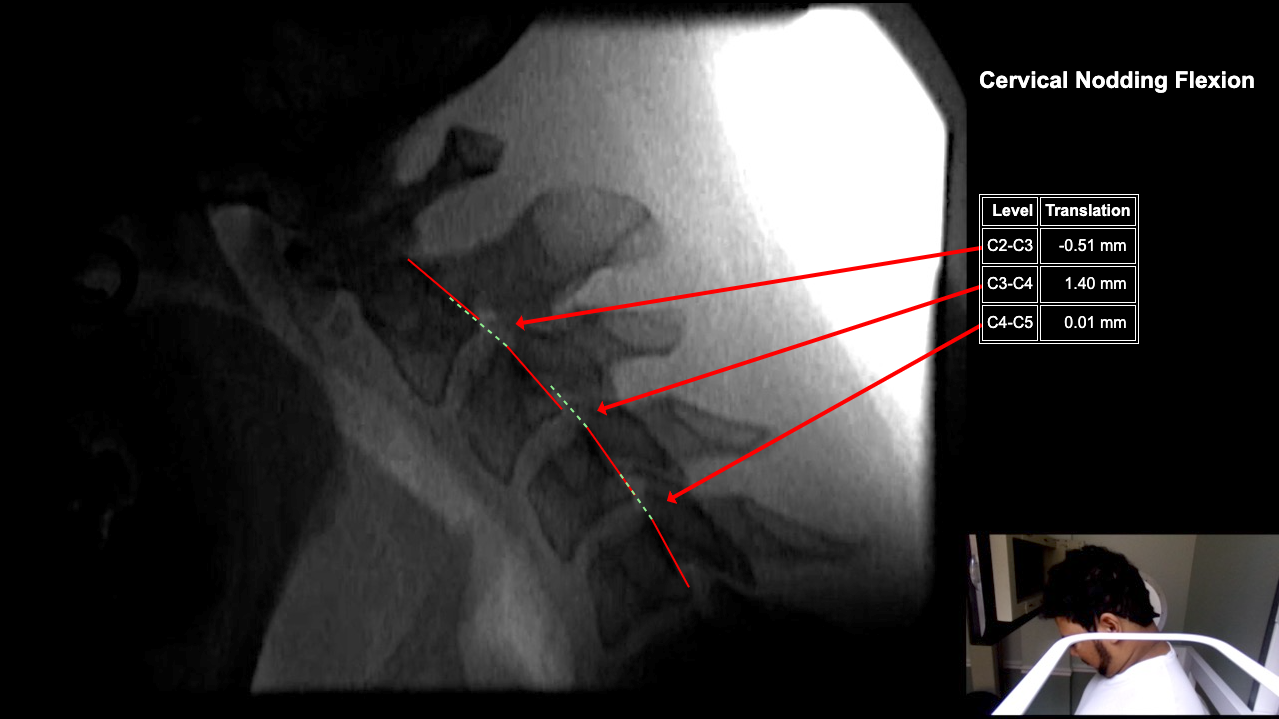

Image Name Image Type Image